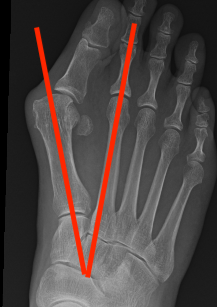

Weight Bearing AP X-ray

Angles

| HVA | DMAA | IMA | HVI |

|---|---|---|---|

|

HVA - hallux valgus angle - metatarsophalangeal angle (MTPA)

Normal < 15o |

Distal metatarsal articular angle

Intermetatarsal angle

Normal < 9o |

Hallux valgus interphalangeus

Normal <10o |